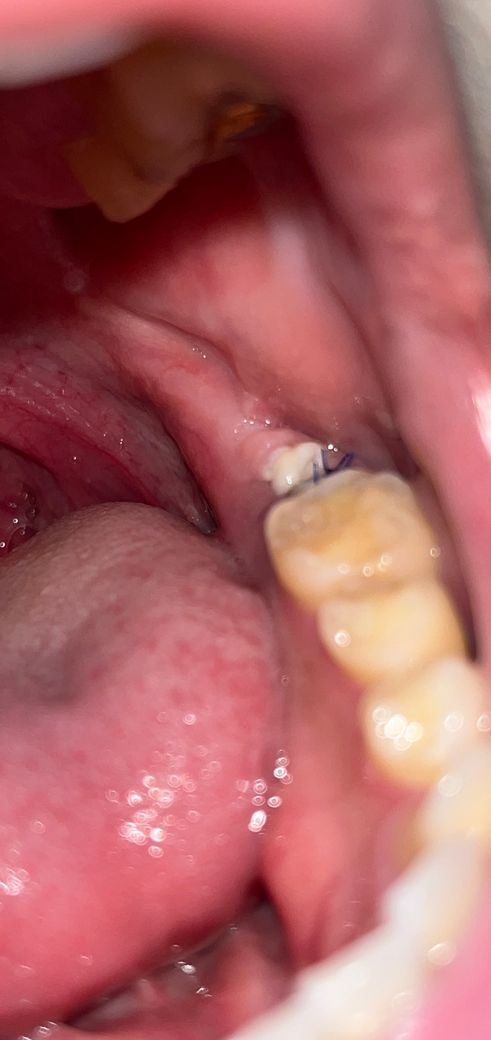

안녕하세요 현재 뼈이식 및 임플란트 식립 후 아직 일주일이 지나지 않아 실밥을 풀지 않았습니다 근데현재 끝쪽에 하얀색이 있는데 무엇 일까요?

• 1번 째 사진

정확하게 무엇인지 알기는 어렵습니다. 다만 전체적인 잇몸의 회복새는 괜찮아 보입니다.

정상적인 창상 회복으로 인한 잇몸 모양일 수도 있으며, 뼈이식을 하고 난 이후에 덮은 membrane 및 재료일 가능성도 있습니다. 주변 잇몸 색을 보았을 때 크게 문제가 되지 않아 보이나 정확한 것을 판단하기 위해서는 시술한 치과를 방문하여 검사를 해보셔야 합니다.

임플란트라고 골 이식을 하는 도중에 골 이식을 한 부위를 안정화시키기 위해서 멤브레인을 사용하는 경우가 있습니다 이런 멤브레인이 잇몸이 잘 아물지 않게 되면 밖으로 튀어나와서 사진처럼 하얗게 볼 수 있습니다 해당 부위를 자극하지 않는 것이 좋으며 치과에서 진료를 받아 보는 것이 좋습니다

잇몸이 치유되는 과정중에 생기는 자연스러운 현상이니 너무 걱정은 안하셔도 될것같습니다.